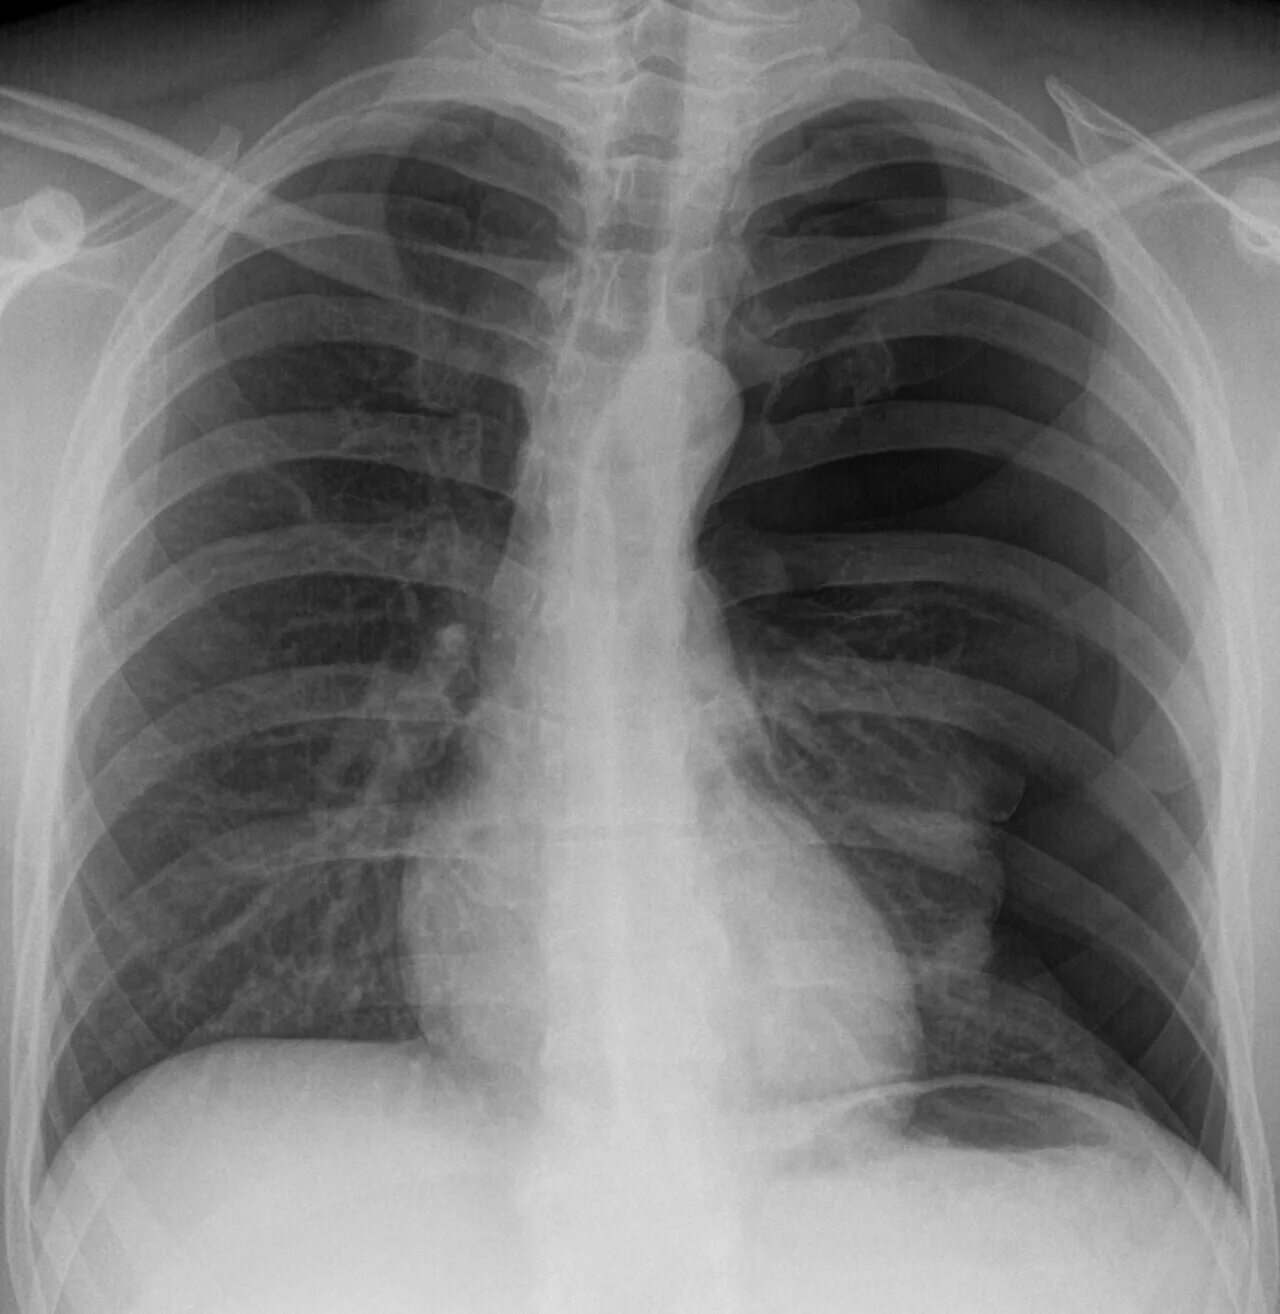

Коллабированное легкое при пневмотораксе